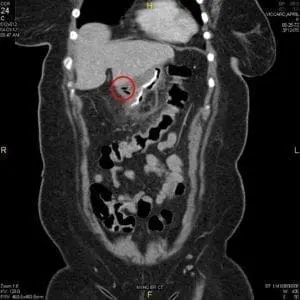

- CT scan

A CT scan is often the first test done when staple line leaks after bariatric surgery are suspected. In the image above next to the red circle you can see a bright white line, which is the staple line. Within the red circle you can see some air bubbles (which appear black). These air bubbles are outside of the staple line, showing that some air that the patient swallowed is now outside of the sleeve.

CT scans are good not only for finding staple line leaks after bariatric surgery, but also for treating them. In some cases the radiologists can insert a small drain tube (called a percutaneous drain) into the area where the leak is, to allow any infection to drain out. This drain is then left in until the leak heals.